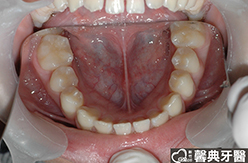

患者︰黃小弟弟,十三歲,學生。

主訴︰戽斗,想做矯正。

治療計劃︰上顎前牙排齊後彈出,下顎前牙排齊後後縮,重建正常咬合關係。